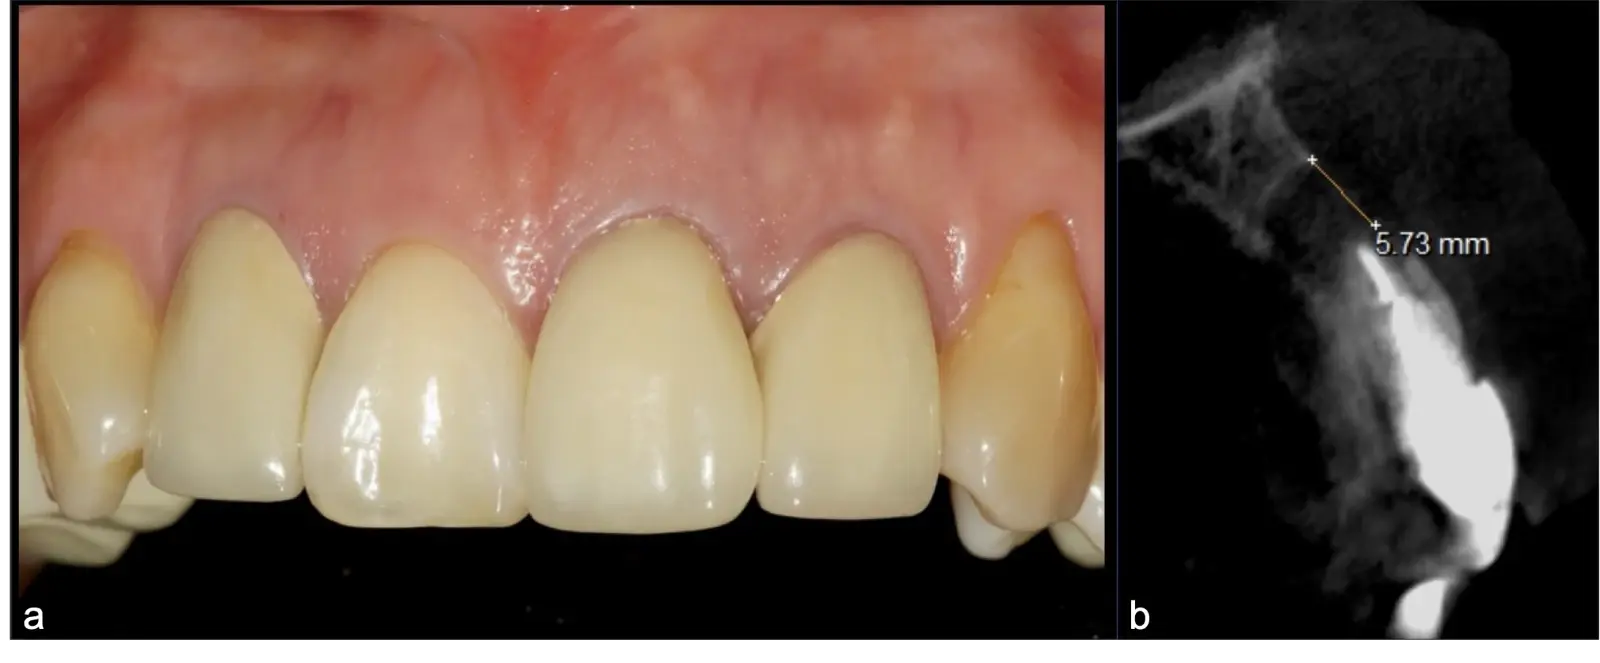

El origen puede ser bacteriano (colonias bacterianas persistentes4, patología periodontal asociada5, reinfecciones por falta de sellado coronal), mecánico (preparación deficiente, fractura de instrumentos, fracturas radiculares6, extravasación de material de obturación7 con ó sin compromiso de estructuras vecinas) y anatómico (conductos accesorios poco permeables o calcificados)8 (Figuras 1 - 4).

La microcirugía endodóntica apical busca conservar la mayor cantidad de longitud de raíz y de hueso circundante sano para no afectar la estabilidad de la pieza.11 Por ello, es ideal el uso de microscopios, elementos de magnificación, instrumental específico (insertos de ultrasonido endodónticos) y materiales de sellado eficientes para el tratamiento retrogrado. Su éxito es alto y evidencia una cicatrización ósea completa en el 74% de los casos al año de tratamiento.12 Cabe destacar que este logro está asociado también, a predictores propios de cada paciente, como la edad, tipo de pieza, profundidad de sondaje y extensión de la lesión.1 El uso complementario de la tomografía computarizada es resaltante como el instrumento imagenológico de elección para la etapa de planificación microquirúrgica,13 ya sea para una ejecución a mano alzada o con guías prefabricadas.14,15